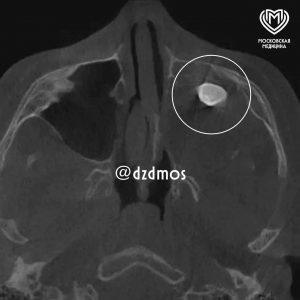

Московские врачи удалили зуб, который обнаружился в носу у подростка. Это оказалось редкой тератомой. Подробности уникального случая...